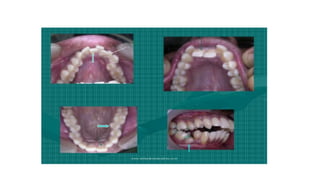

Types of Malocclusions •Overcrowding.Overcrowding is a common condition typically caused due to lack of space resulting from overlapping or crooked teeth. •Spacing. ... •Openbite. ... •Overjet. ... •Overbite. ... •Underbite. ... •Crossbite. ... •Diastema.